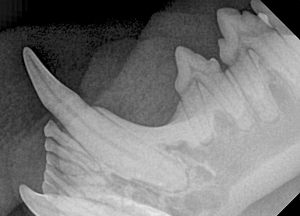

Feline Full Mouth Radiograph example